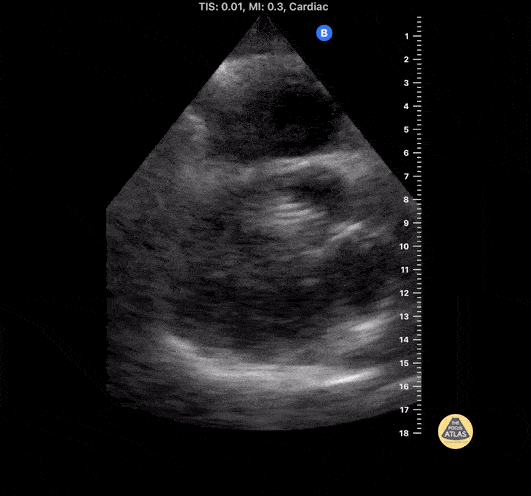

Middle aged male with recent right iliac DVT s/p thrombectomy and venous stent placement is found to have asymptomatic migration of stent into the right heart. In the subxiphoid view, the hyperechoic coiled-appearing stent is seen traversing the tricuspid valve. Percutaneous attempt at removal was unsuccessful, so he ultimately underwent open-heart surgery. Contributed by: Eric Reid, MD